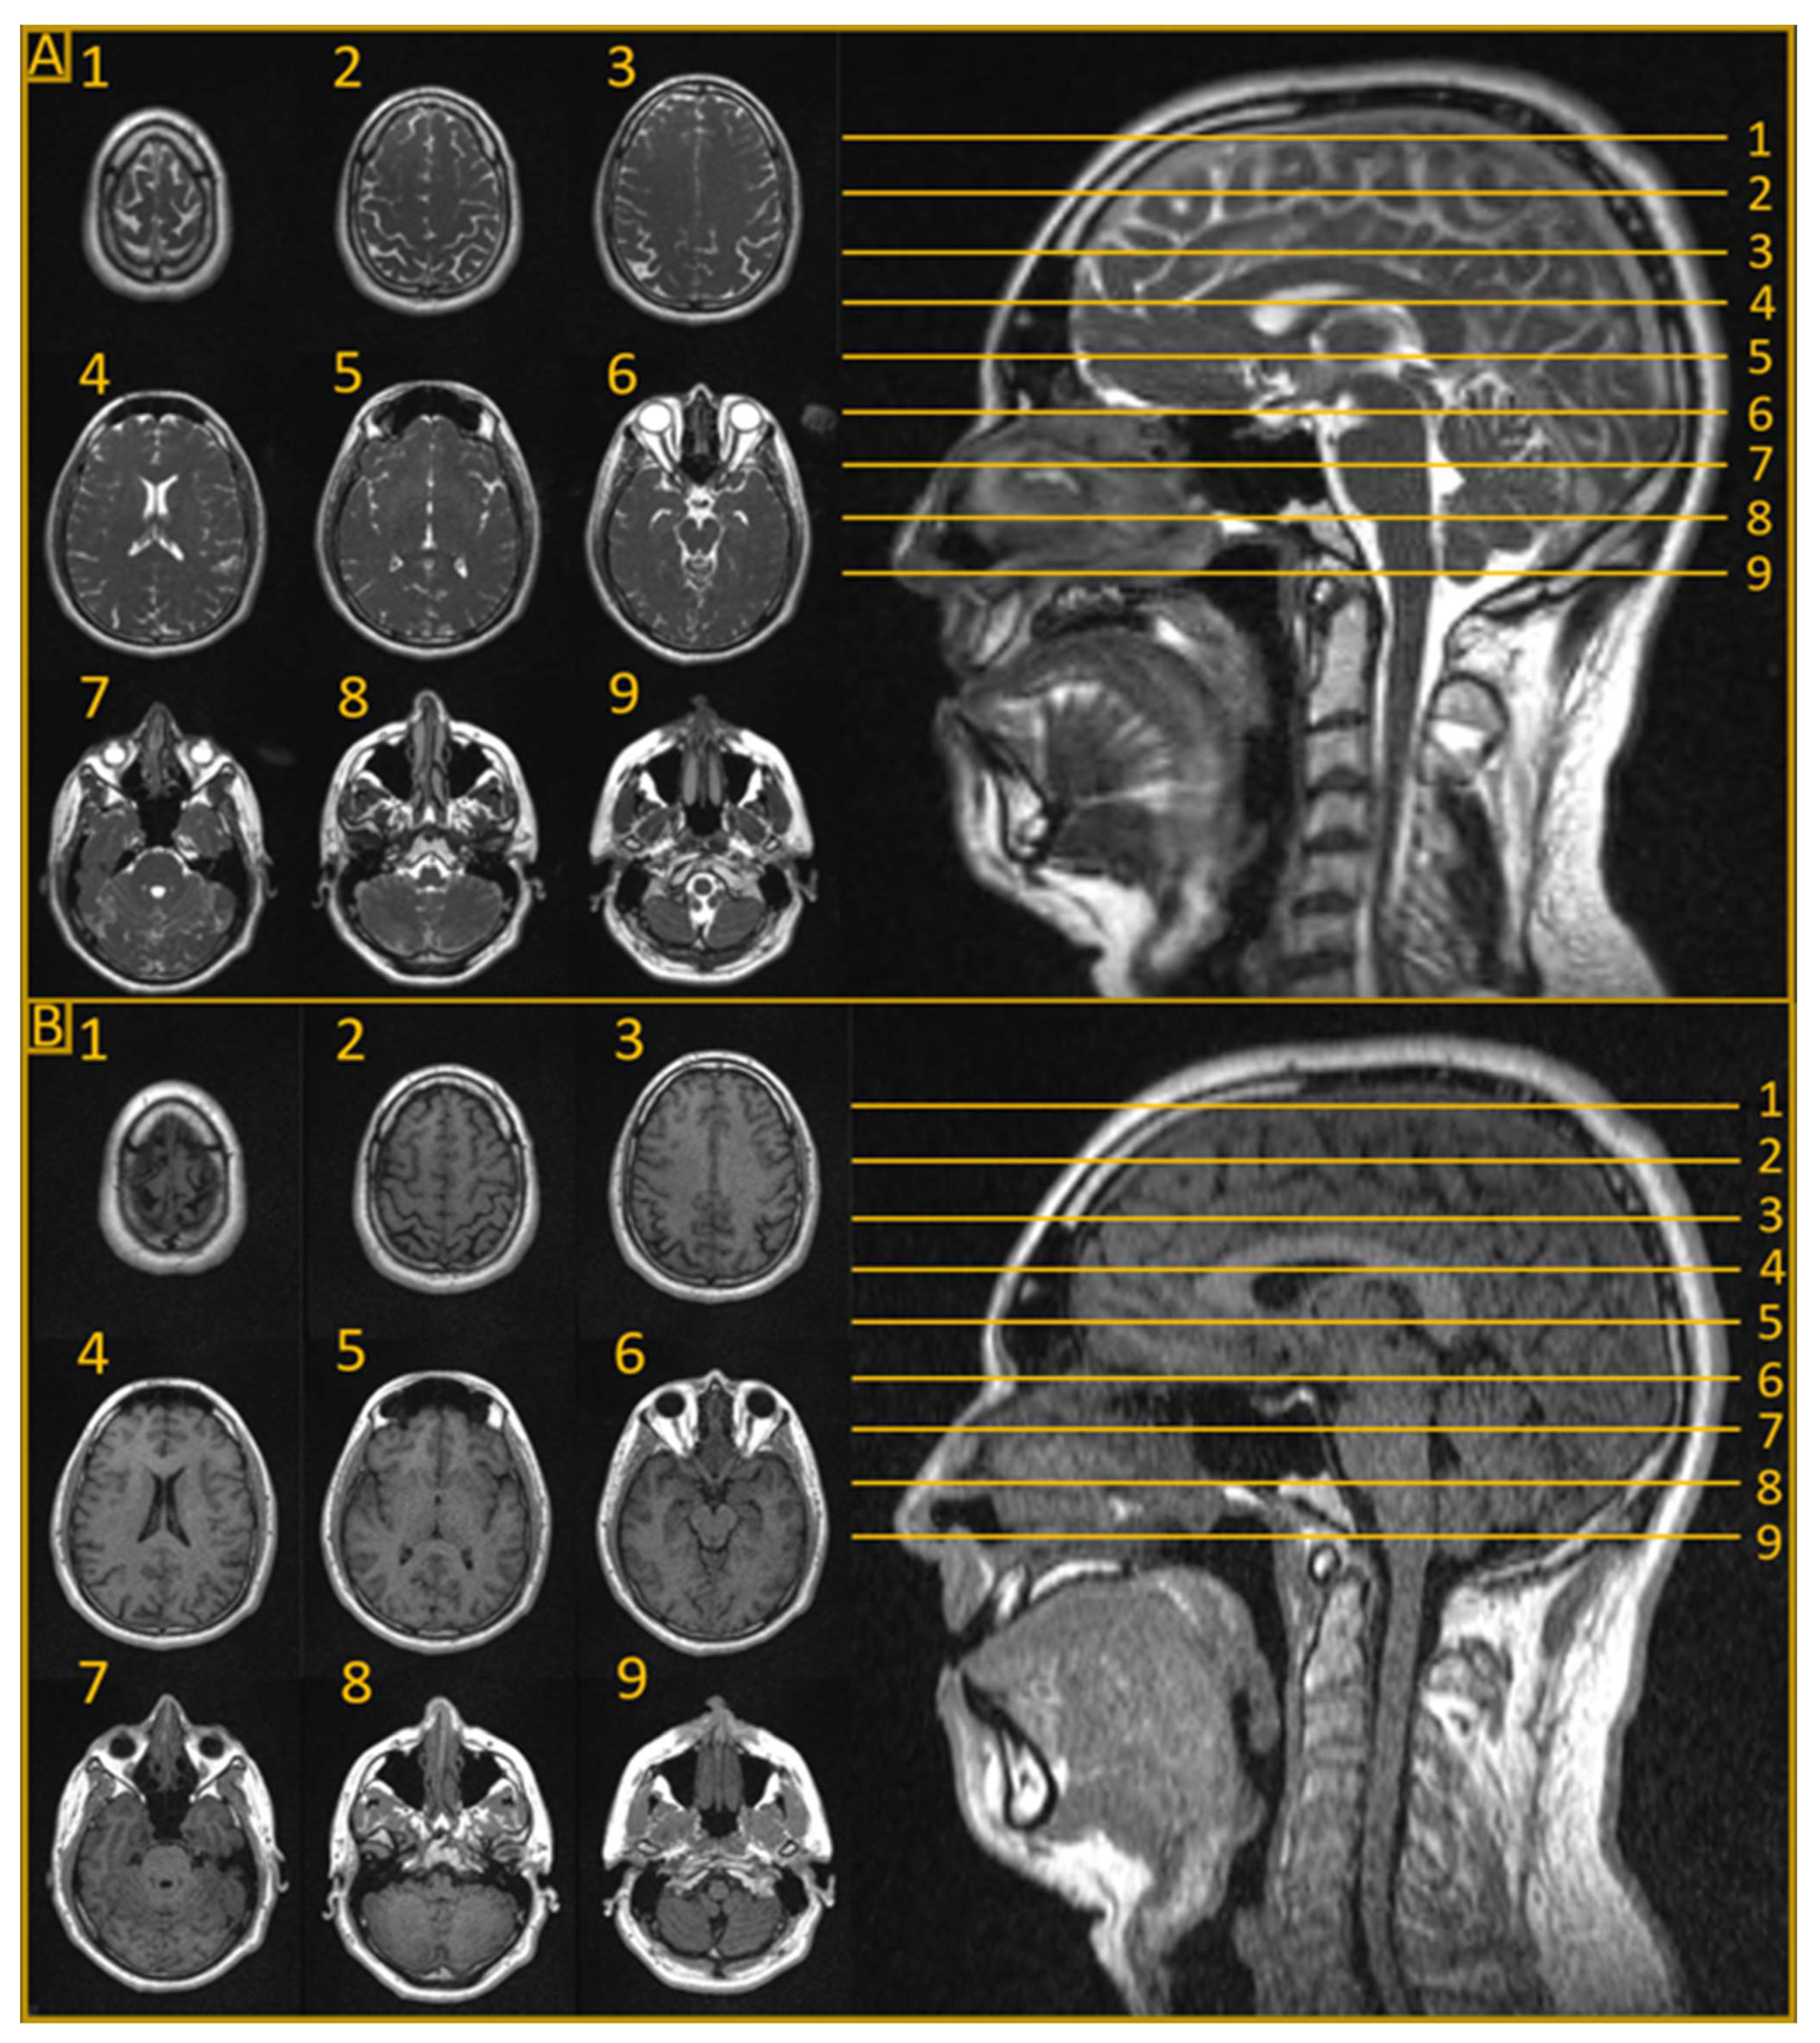

The advent of MRLs marked a revolutionary step in the field of MRgRT for CNS tumors [6,7]. In addition to their soft tissue imaging advantages, MRLs also enable adaptation of treatment plans based on daily intrafraction anatomical changes. These advantages work together to effectively expand the therapeutic window for CNS RT by improving dose delivery to the tumor and minimizing the exposure of surrounding healthy tissue [8,9]. The two commercially available MRLs are the ViewRay MRIdian (ViewRay Technologies Inc., Oakwood Village, Ohio) and Elekta Unity (Elekta AB, Stockholm, Sweden) systems [10]. These systems make up the majority of clinical MRL implementations and have been used with great efficacy to treat tumors across the body [10,11]. The MRIdian system integrates a 0.35 T field strength split-bore magnet MRI with a 6 MV flattening filter-free (FFF) linear accelerator [12], while the Elekta Unity combines a 1.5 T MRI with a 7 MV FFF linear accelerator [13]. As an example of the imaging capabilities of the low-field MRIdian unit, Figure 1 demonstrates a T2 fluid-attenuated inversion recovery (FLAIR) sequence and a true fast imaging with steady-state free precession (TRUFI) sequence [14] of a healthy brain. The Unity system’s conventional strength MRI generates images of similar quality to a 1.5 T diagnostic MRI unit, and the system has access to all clinically available sequences on Philips MR systems. Although both systems have their unique strengths and limitations, they share the same advantages over conventional computerized tomography (CT)-based radiation therapy in the treatment of CNS tumors. These advantages are actively being explored in several innovative trials. Table 1 lists currently active trials exploring CNS radiation therapy on an MRL that are registered on ClinicalTrials.gov (8 August 2023).

Figure 1.

Magnetic resonance imaging (MRI) sequences on a 0.35 T combination MRI and linear accelerator (MRL) without contrast. (A) A true fast imaging with steady-state free precession (TRUFI) sequence of a healthy brain. The in-plane resolution and acquisition time for the TRUFI sequence were 1.5 mm and 1 min and 40 s, respectively. The TRUFI sequence provides contrast that is a combination of T1 and T2 weighting and is the sequence used for planning on the 0.35 T MRL. (B) T2 fluid-attenuated inversion recovery (FLAIR) sequence of a healthy brain. The in-plane resolution and acquisition time for the FLAIR sequence were 0.75 mm and 12 min and 6 s, respectively. Both sets of images (FLAIR and TRUFI) have a slice thickness of 1.5 mm and were acquired using a six-channel phased-array receiver head coil.